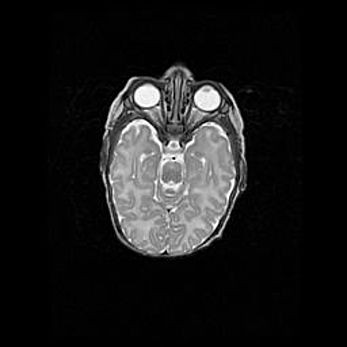

Неполная лизэнцефалия (пахигирия). Открытая гидроцефалия.

Возраст: 17 дней

Вес: 3110 г

Пол: мужской

Окружность головы: 33,5 см

Срок гестации: 35-36 недель

Лизэнцефалия—недоразвитие корковой пластинки и мозговых извилин в результате нарушения миграции нейронов коры. Поверхность мозговых полушарий гладкая. Микроскопически выявляется отсутствие нормальных слоев коры и скопление групп нейронов в подкорковом белом веществе.

Пахигирия—уменьшение числа вторичных извилин. В пораженном полушарии нервные клетки образуют толстый недифференцированный слой с неправильно расположенными нервными волокнами и группами гетеротопных клеток. Нервные клетки незрелые. Белое вещество истончено. При этом нередко аномально развит корково-спинномозговой путь.